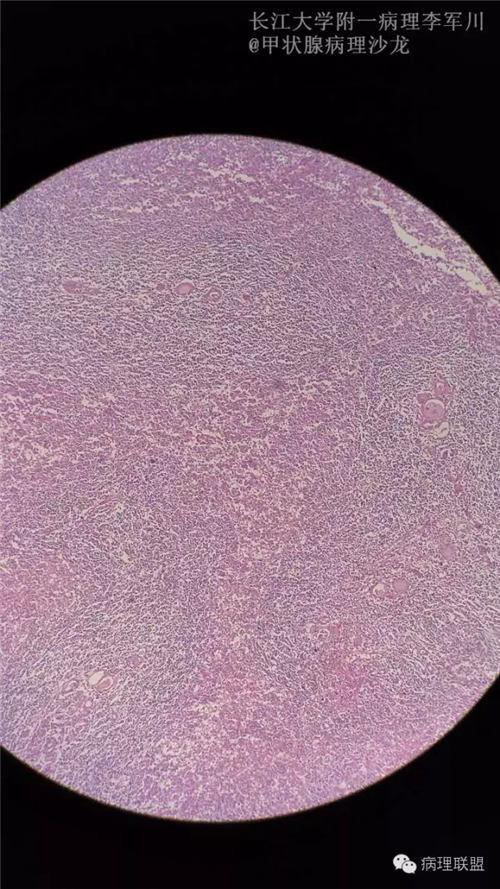

甲状腺病变中的MALT?

女,40余岁,右侧甲状腺肿块,直径约3cm。